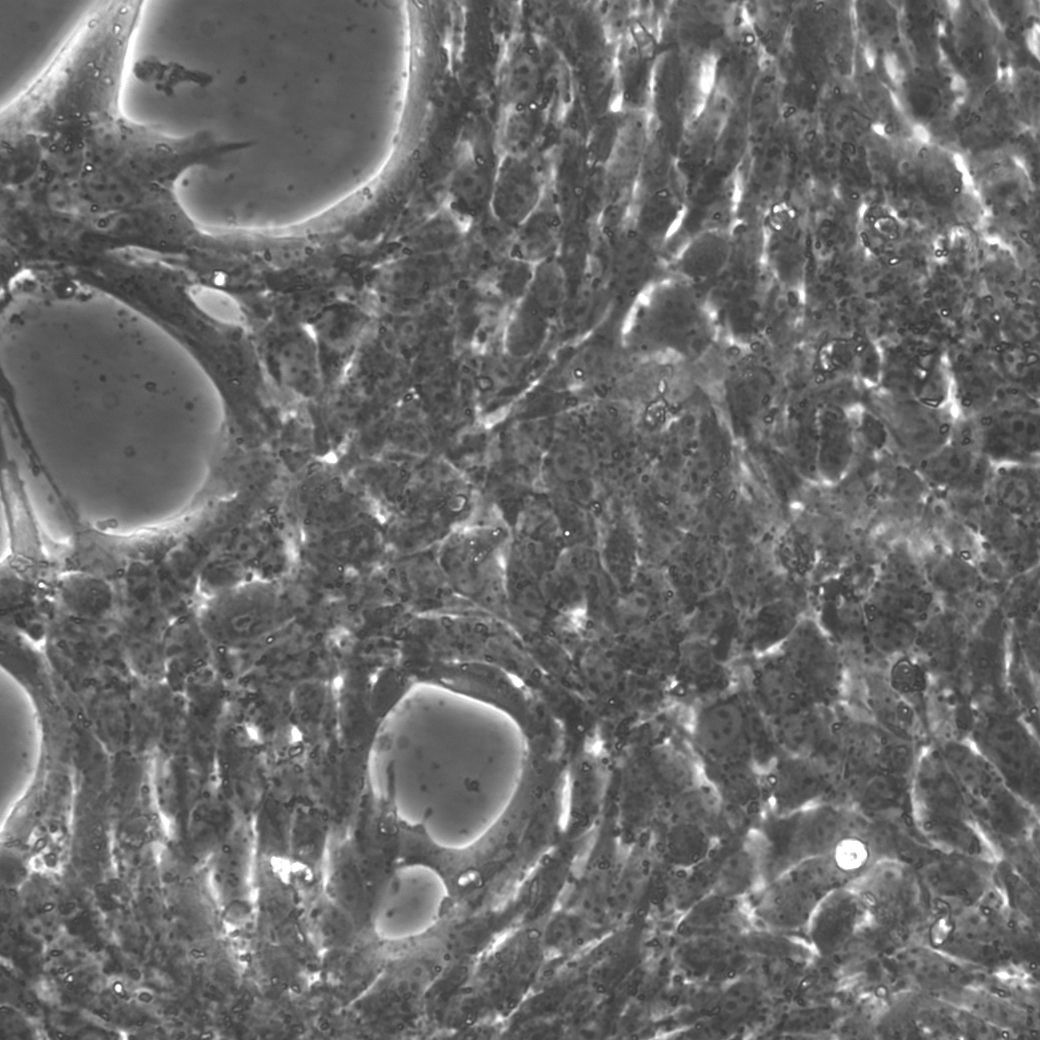

| 细胞形态 |

上皮样细胞,贴壁生长 |